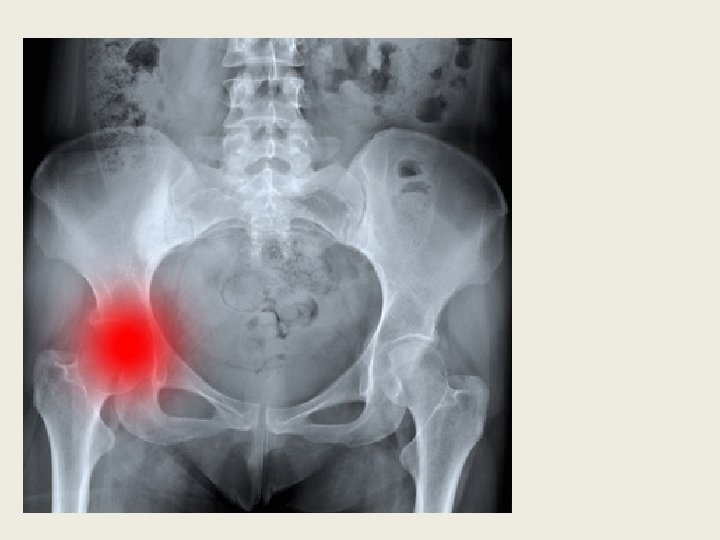

Развивается артроз тазобедренных суставов (коксартроз) обычно после сорока лет. Женщины болеют чуть чаще, чем мужчины. Коксартроз может поражать как один, так и оба тазобедренных сустава. Но даже в случае двустороннего поражения сначала, как правило, заболевает один сустав, и лишь потом к нему «подтягивается» второй. Основной симптом коксартроза — боль в паху. Чаще всего боль из паха распространяется вниз по ноге по передней и боковой поверхности бедра. Иногда такие болевые ощущения распространяются еще и на ягодицу. Обычно боль, идущая от паха по передней и боковой поверхности бедра, доходит вниз только до середины бедра или до колена. Ниже колена эта боль почти никогда не идет. Лишь очень редко боль доходит до середины голени, но не опускается до пальцев ног — в этом отличие коксартрозной боли от боли, вызванной повреждением поясницы (например, грыжей межпозвонкового диска). Боли возникают в основном при ходьбе и при попытке встать со стула или с кровати. Часто именно самые первые несколько шагов после вставания бывают особенно болезненными. Потом, когда болеющий человек расходится, ему может стать чуточку полегче. Но после долгой ходьбы болевые ощущения вновь

На ранних стадиях коксартроза болевые ощущения в паху и бедре выражены слабо, чаще отмечается лишь легкое прихрамывание и несильная ноющая боль при ходьбе. Поэтому заболевший человек не спешит к врачу, надеясь на то, что проблема каким то образом разрешится сама собой. Однако идет время, болезнь прогрессирует, и боле вые ощущения нарастают. В большинстве случаев это происходит постепенно, но иногда, после неудачного движения или нагрузки, могут происходить довольно резкие обострения, которые длятся от нескольких дней до нескольких месяцев. Постепенно к болевым ощущениям добавляется ограничение подвижности больной ноги. Заболевшему человеку трудно отвести ногу в сторону, подтянуть ногу к груди; трудно надеть носки или обувь. Заболевший человек вряд ли сможет сесть на стул «верхом» , широко раздвинув ноги — или сделает это с большим трудом. По мере прогрессирования коксартроза у может появиться все более отчетливый хруст в больном суставе при движении и ходьбе. Обычно он бывает связан с трением суставных поверхностей, не идеально подогнанных друг к другу по форме. Конечно, у некоторых людей суставы могут и без коксартроза пощелкивать, и весьма громко. Но артрозный хруст имеет совсем другую тональность, он грубый и «сухой» . И если на первой стадии